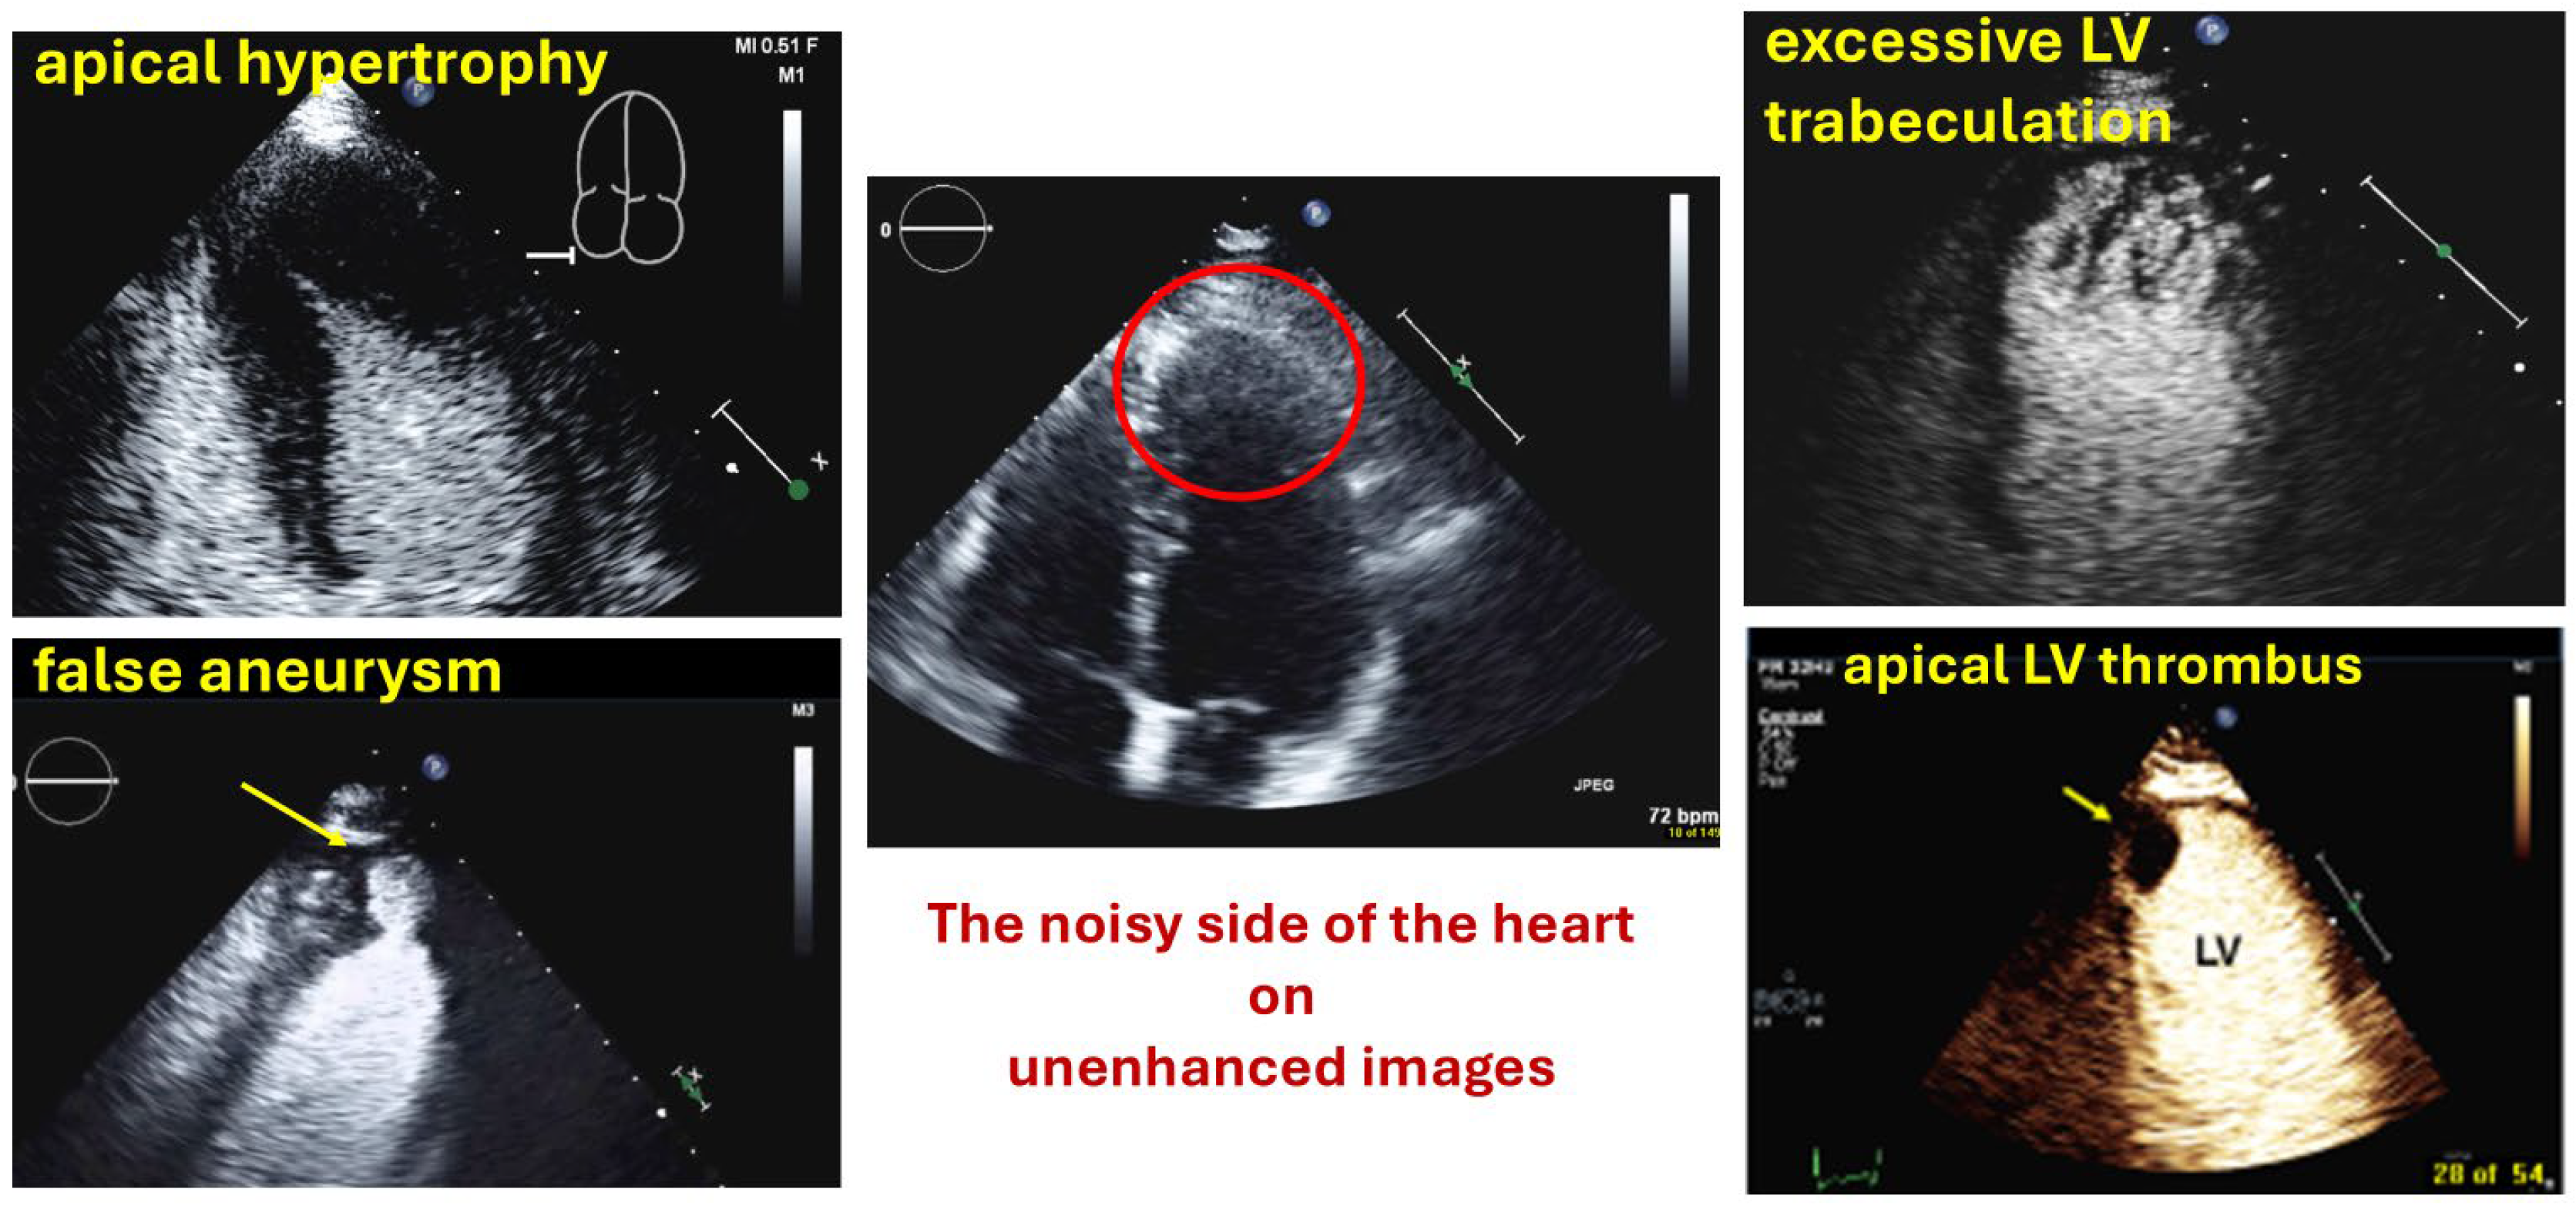

| Myocardial disease and masses |

| Thrombi |

| Apical hypertrophy |

| Pseudoaneurysm |

| Myocardial rupture |

| LV diverticula |

| Excessive LV trabeculations |

| Typical findings | Clear demarcation from the normal myocardium Narrow neck of false aneurysms Search for associated thrombi and pericardial effusion (more likely near false aneurysms) |

| Typical finding | 1. Hourglass/ace-of-spades shape of apical LV cavity 2. Apical myocardium appears dark in late systole due to compression of the intramyocardial vessels 3. Apical aneurysms +/− thrombi in some patients |

| Typical findings | trabeculated layer apical, lateral, and inferior: more than 3 trabeculations, ratio of trabeculated/compact myocardium >2 The number of trabeculations and the ratio of trabeculated/compact myocardium does not seem to impact clinical management |